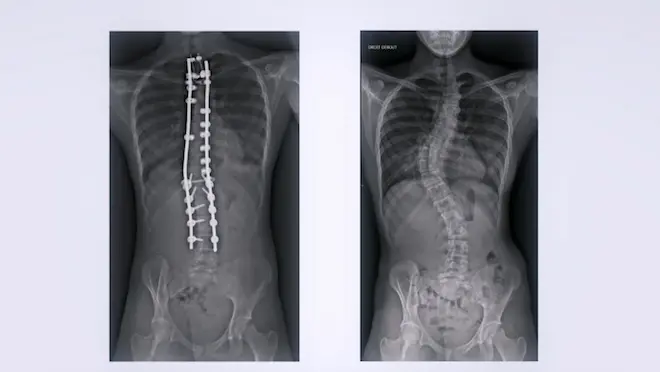

À 15 ans, Julia souffre de la malformation orthopédique la plus fréquente chez l'adolescent : la scoliose. Depuis la puberté, sa colonne vertébrale ne cesse de se tordre. Elle est aujourd'hui tellement déformée qu'elle fait souffrir la jeune fille, et qu'elle menace, à terme, de l'handicaper lourdement. Julia n'a plus le choix. Soutenue par Marie et Olivier, ses parents, elle a dû se résoudre à la chirurgie.

Une chirurgie impressionnante et extrêmement délicate, puisqu'elle consiste à fixer des tiges en titane dans sa colonne vertébrale, à quelques millimètres à peine de sa moelle épinière. Un petit écart de trajectoire et c'est toute la motricité de la jeune fille qui est menacée.

- Une plongée dans l'anatomie

Pour bien comprendre cette chirurgie complexe, des animations 3D montrent ce que la caméra ne peut pas saisir.